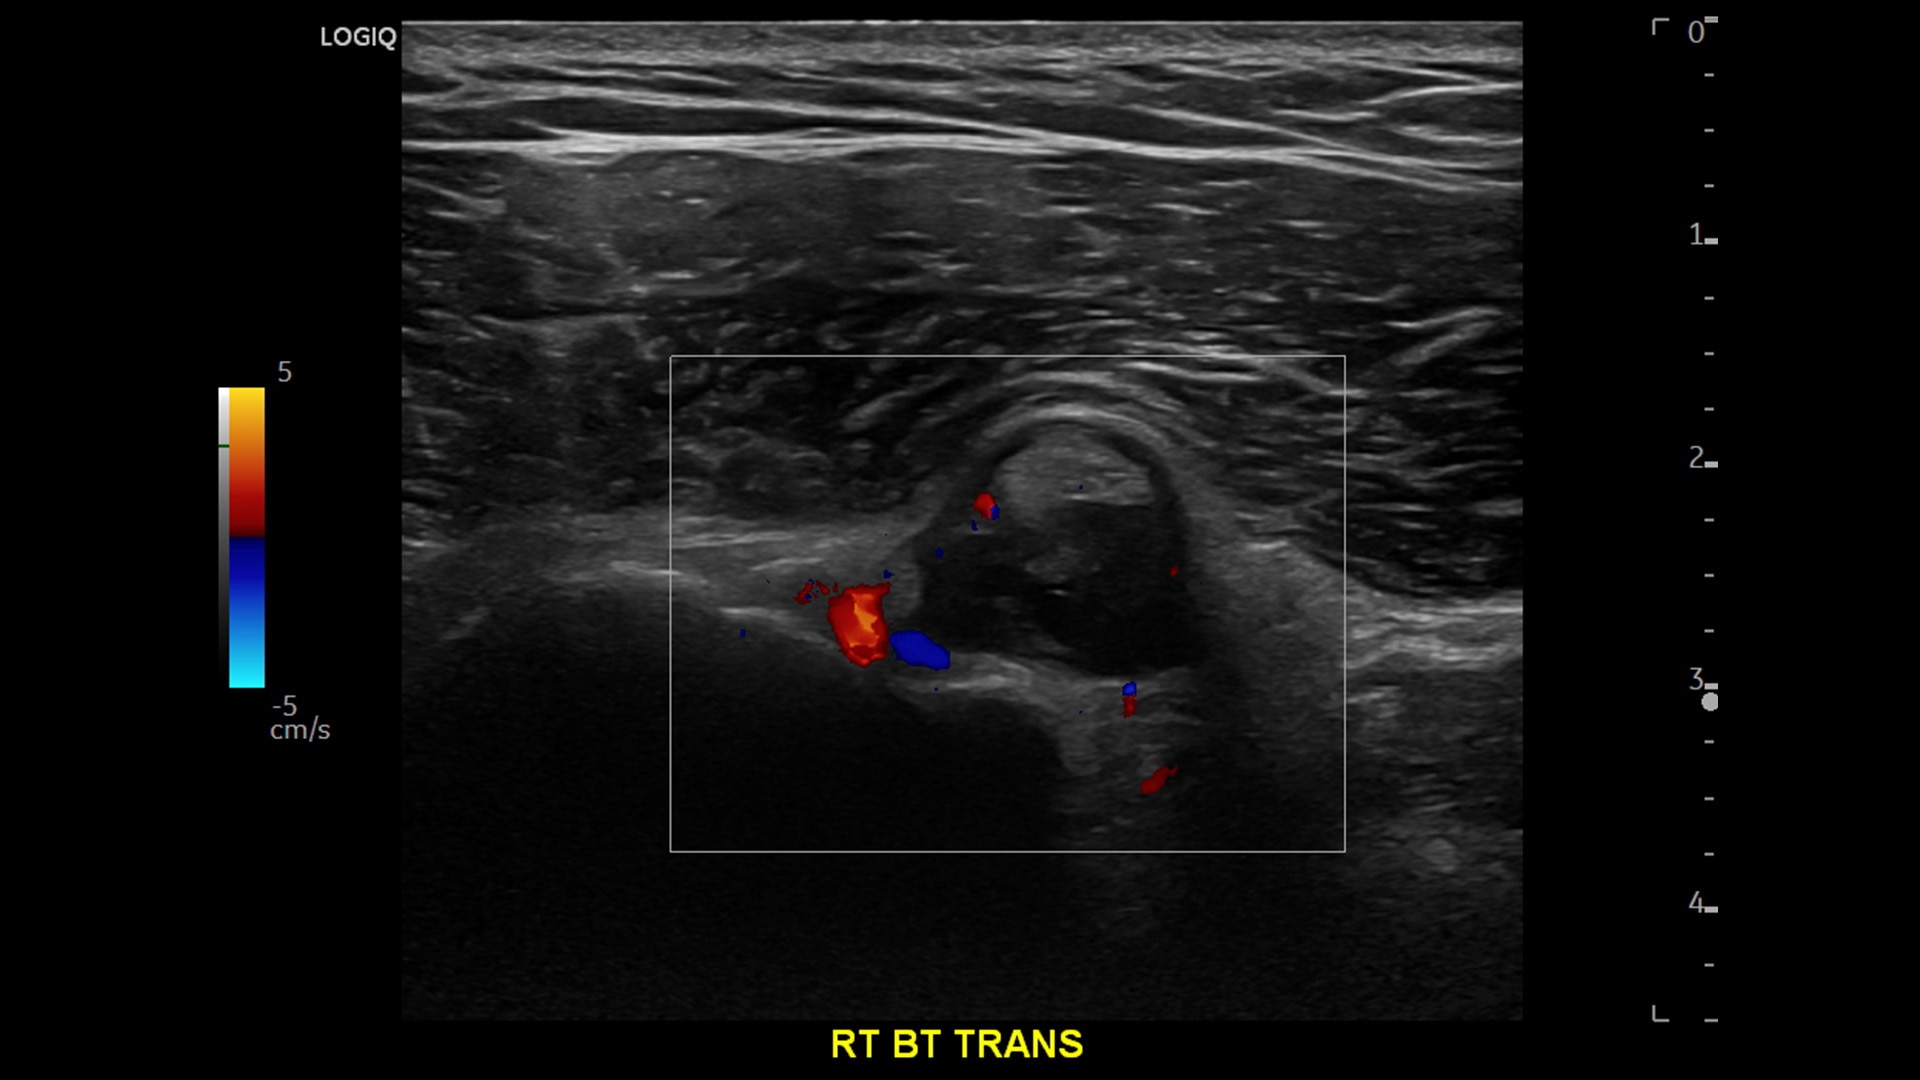

Strength and power to enhance clinical capabilities and deliver exceptional image quality